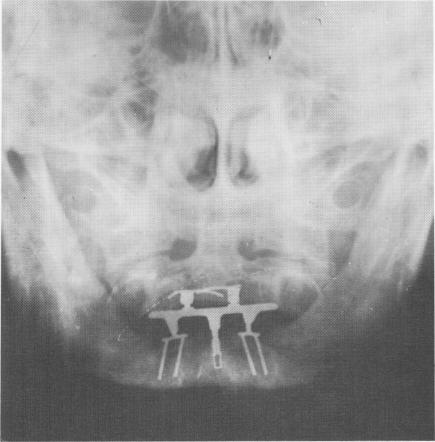

Fig. 5-57. Both implants are in place with the connecting bar bridging them. The prosthesis is fashioned over the bridge. Here Linkow also used a vent-plant to help offset bucco- and labiolingual movements.